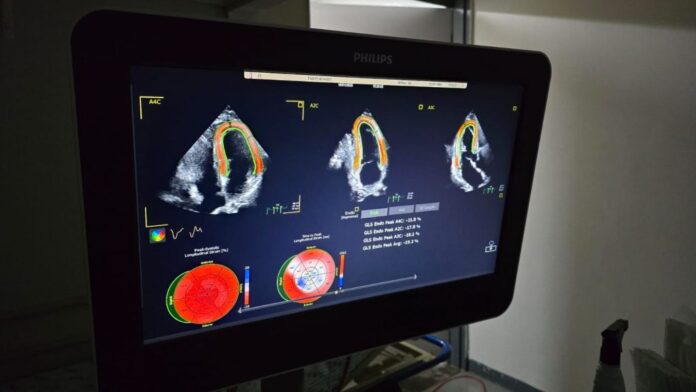

O Hospital Regional de Mato Grosso do Sul (HRMS) passou a operar com um novo aparelho de ecocardiograma de tecnologia avançada, destinado a aumentar a precisão dos diagnósticos e a qualificar o atendimento cardiológico no estado.

O equipamento foi adquirido com recursos de emendas parlamentares, complementados por contrapartida do Governo do Estado. Segundo a assessoria do hospital, ele oferece recursos para análises mais detalhadas das estruturas cardíacas e do fluxo sanguíneo, com imagens de maior definição e maior agilidade na realização dos exames.

O HRMS, referência em atendimento de alta complexidade, também reforçou a área de cardiopediatria com a nova tecnologia. O aparelho dispõe de sondas específicas para diferentes faixas etárias, incluindo recém-nascidos e prematuros, o que contribui para a identificação mais precisa de cardiopatias congênitas e para a definição de tratamentos adequados.

O serviço de Cardiodiagnóstico atende pacientes de todo o estado, tanto por meio da regulação da rede pública quanto internados na própria unidade. A implantação do novo ecocardiograma amplia a capacidade de resposta em cardiologia clínica e pediátrica, promovendo exames mais detalhados e maior segurança na condução dos casos.